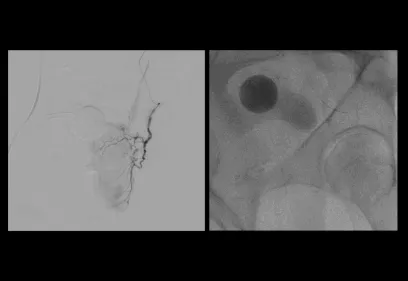

Cover image of a body scan of IMAGES magazine

IMAGES

Images is an annual publication on milestones and progress in radiology.

Read the latest issue